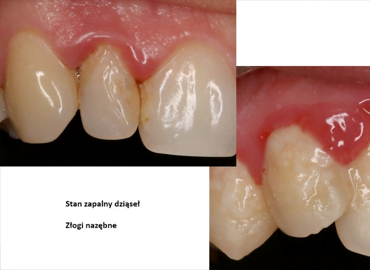

Nie jesteśmy wstanie samodzielnie, w warunkach domowych dokładnie doczyścić kieszeni dziąsłowych. Gromadząca się płytka nazębna w tych miejscach to „siedlisko” bakterii. Bakterie namnażają się, powodując w pierwszej kolejności stan zapalny dziąseł.

Wczesnym objawem zapalenia dziąseł jest obrzęk, delikatne krwawienie. Następnie pojawiają się głębokie kieszenie dziąsłowe, które dodatkowo utrudniają prawidłową higienę jamy ustnej, co potęguje stan zapalny dziąseł. Kolejnym etapem zapalenia jest ból oraz stopniowa destrukcja kości, czego następstwem jest rozchwianie zębów.